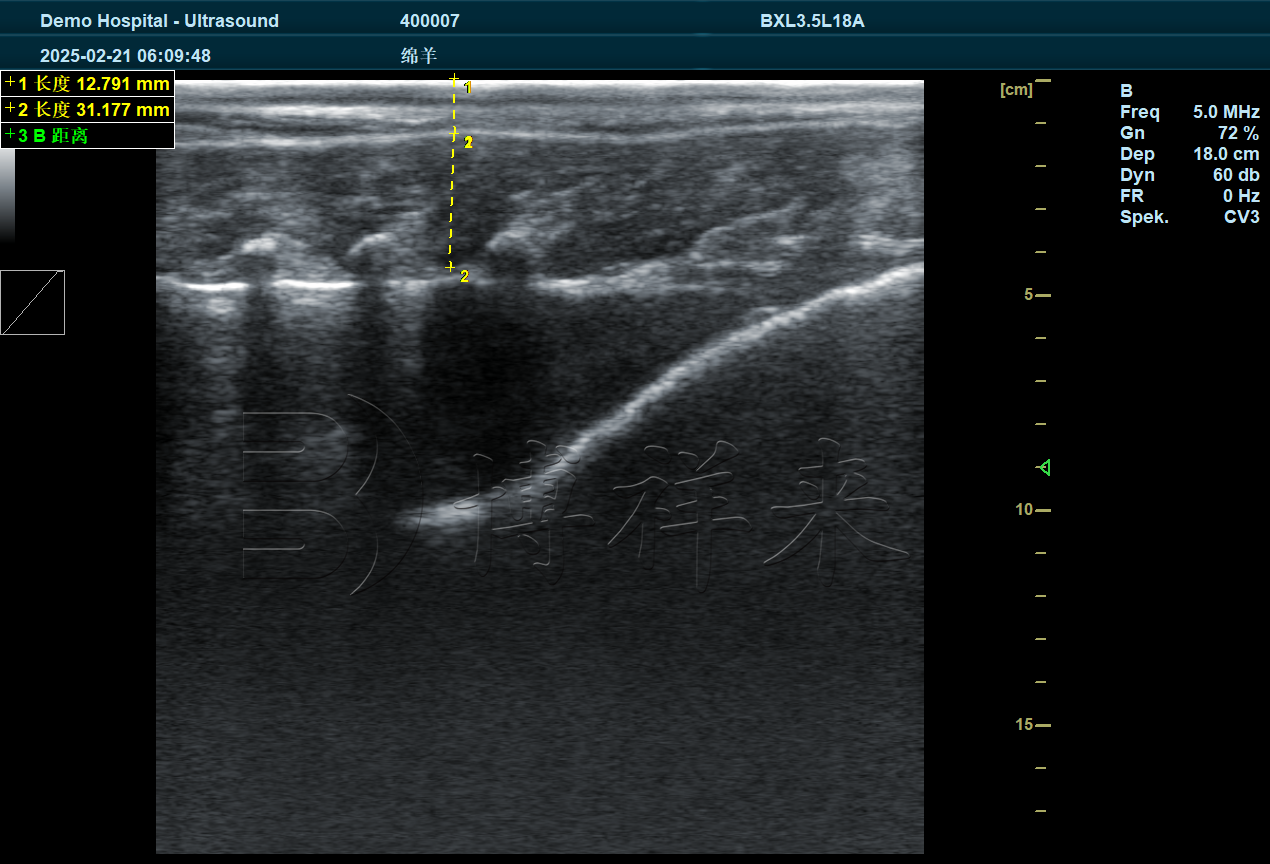

优质的羊背膘仪图像应能看到:皮肤层 → 脂肪层 → 肌肉层三层结构。

将探头垂直贴在第 12–13 肋间位置,让图像横截面显示背部肌肉结构。羊的背膘层通常呈均匀浅回声,肌肉层呈纤维状中等回声,界限清晰。

4. 测量背膘厚度与眼肌宽度

羊背膘仪大多具备自动测量功能,只需点选图像上脂肪层的上下边界即可自动获得数据。

一些更高端的仪器(如博祥来新推出的多功能背膘仪)可直接:

自动标记脂肪层

自动计算眼肌宽度与高度

自动输出数值与图像

让检测更高效、更标准。